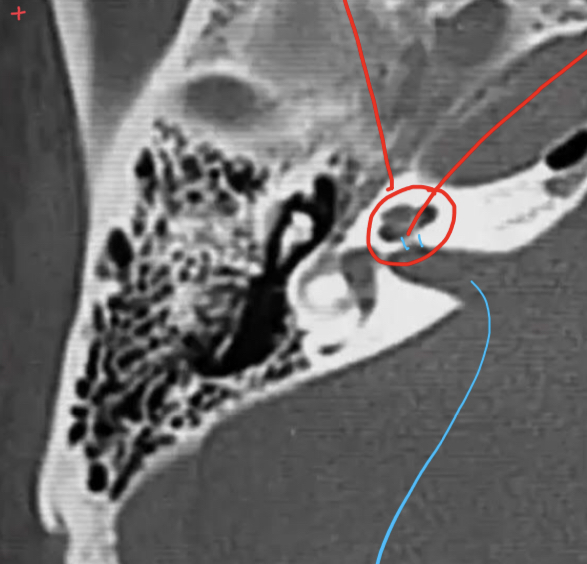

What are the ossicules of middle ear?

Description?